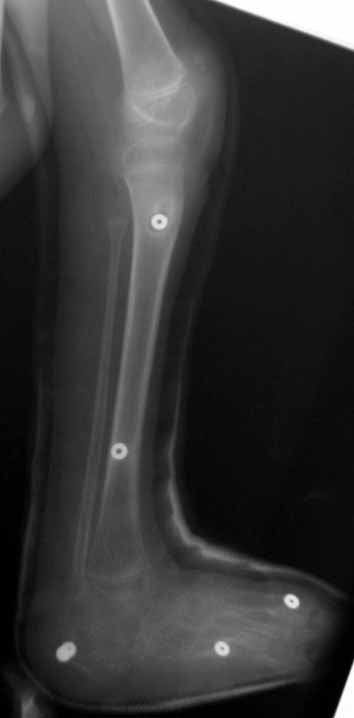

Using the Ilizarov method, foot deformities can be corrected either with or without osteotomy. The system without osteotomy corrects deformities through joints. This technique can be used in patients smaller than 8 years of age and without fixed bony deformity. For patients older than 8 years of age with fixed bony deformity and patients with neuromuscular diseases, in whom maintaining soft tissue correction is very hard, osteotomy is required.

If there is no coexisting deformity, the duration of external fixation depends on the type of defornity and the correction method (with o without osteotomy) of the foot. If the deformity is associated with other lower limb problems such as shortness, the duration of treatment depends on the secondary procedures rather than correction of the foot deformity.